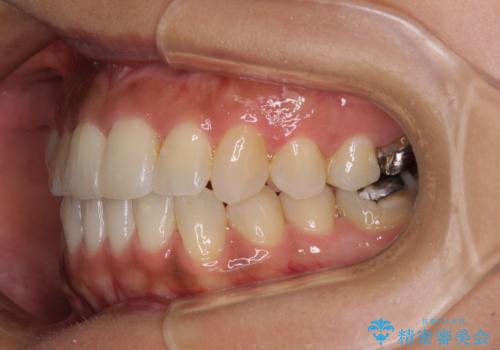

骨格的な問題を解決したことで、下顎は部分矯正で対応することができました。

上顎骨の横幅が狭く、歯列が混み合っていたため、急速拡大装置により側方拡大し、咬み合わせと歯列を改善することとしました。

下顎は部分的に咬み合わせに問題があったため、部分的な装置を付けることとしました。